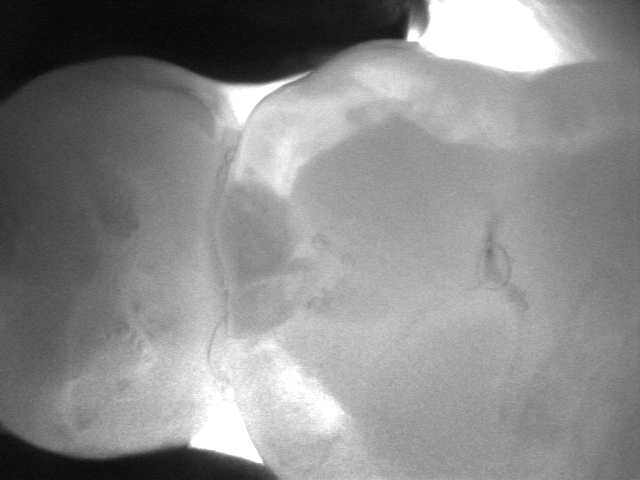

La videocamera digitale sulla testa del manipolo rileva luci ed ombre all’interno del dente e proietta l’immagine ottenuta sullo schermo del pc in tempo reale: le parti sane, che consentono il passaggio della luce, risultano chiare, quelle lesionate, che al contrario lo bloccano, si distinguono nettamente come aree scure.

Le immagini in bianco e nero, altamente dettagliate, ricordano molto le radiografie ma di fatto sono state del tutto ottenute senza radiazioni, soltanto per transilluminazione laser!

Vedere l’estensione della lesione, se ancora soltanto sullo smalto o già sconfinata in dentina, e la sua esatta posizione sono informazioni fondamentali per impostare una terapia che sia il più possibile conservativa.

Consente la diagnosi precoce di cracks (incrinature, fratture), demineralizzazioni e carie (occlusale, prossimale o secondaria sotto vecchi restauri), quando sono sopragengivali.

Evidenzia la carie con più sensibilità e attendibilità della sola ispezione visiva e molto prima che appaia alle radiografie, rendendo possibili trattamenti profilattici o minimamente invasivi.